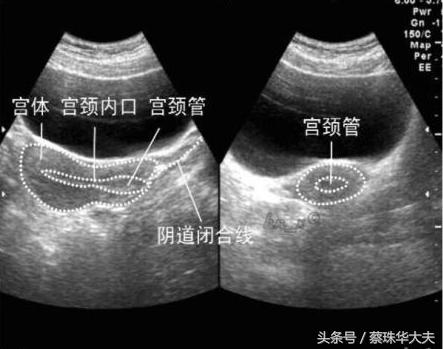

而腹部探头(神探妈妈)虽然有时候比小神探厉害,但神探妈妈眼睛看表面东西厉害,找深部东西没有小神探那么灵活。

神探妈 妈看子宫和卵巢输卵管只有通过肚皮皮肤,肚皮下脂肪,才能照到达子宫表面,而且有时候爱捣乱的肠子还会来砸场。

所以神探妈妈只能找来帮手,让膀胱充满尿才能推开爱捣乱的肠子。但这个膀胱助手也不是个省游的灯,膀胱里的尿太少,神探妈妈嫌弃这个助手不得力,尿太多,主人受不了。只能凑活着看吧。